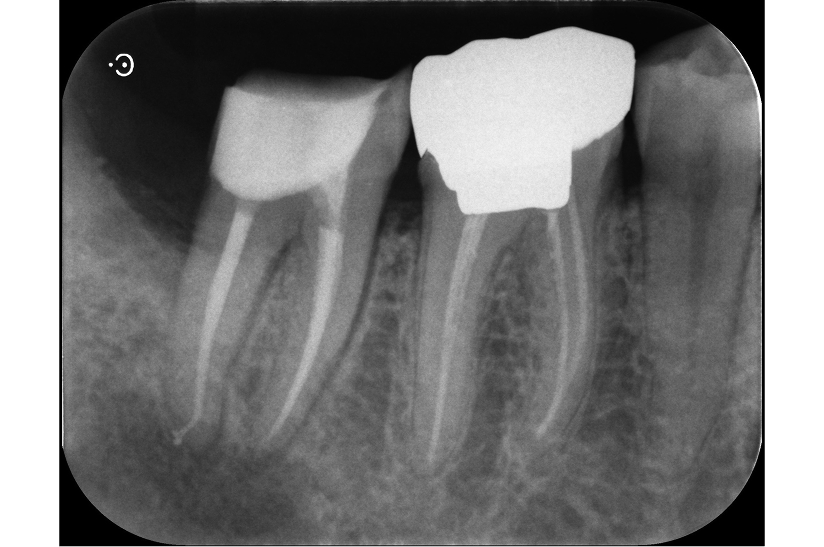

長期予後を見越した根管治療の症例

タップで写真の拡大ができます。

Before

After

主訴

症状はないが、治療が必要な箇所があればしっかり治療しておきたい。

治療内容

イニシャルトリートメント(根管治療・大臼歯)、ファイバーポストコア、セラミッククラウン

治療期間

3ヶ月

治療費用

352,000

治療の

リスク

根尖部透過像が完全に消失しない可能性があります。